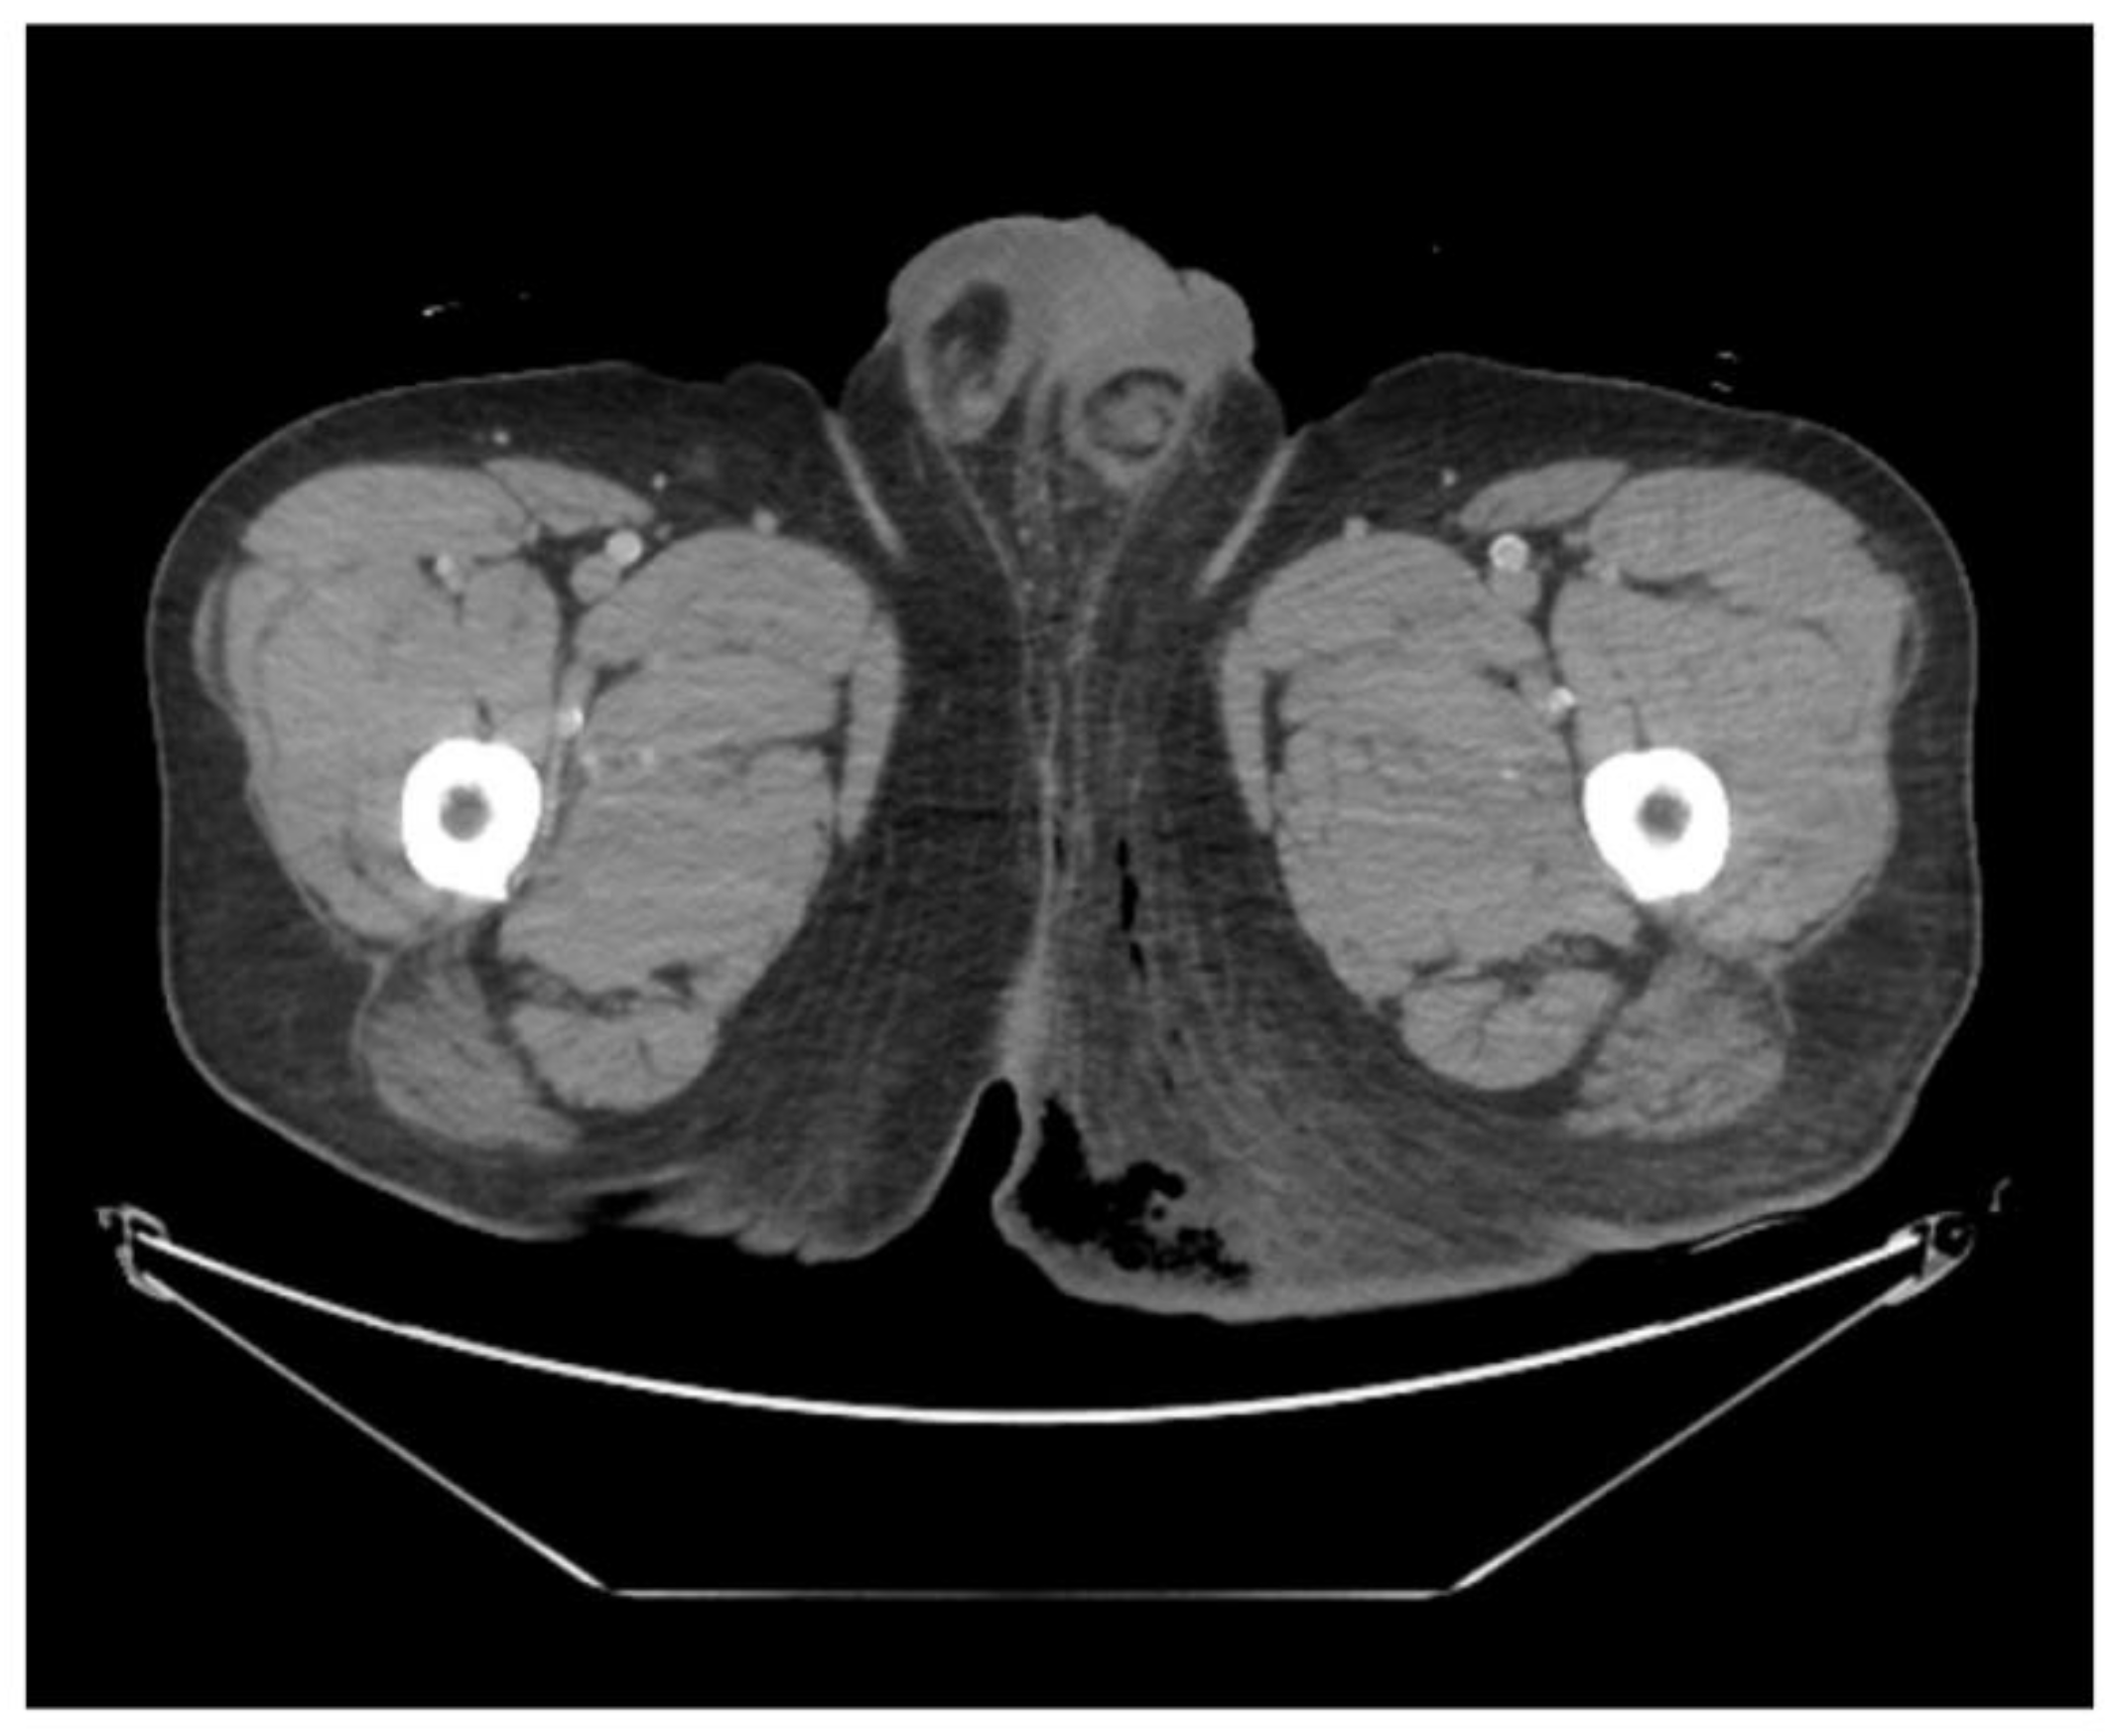

A man in his 40s presented to the emergency department complaining of severe perineal pain and pus discharge from multiple sites in the perineum. The patient had undergone surgery for fistula at another clinic a week ago. He reported a medical history of diabetes, hypertension, and heavy alcohol consumption. Physical examination revealed an edematous scrotum with a foul-smelling exudate. Pelvic computed tomography (CT) revealed air collection in the buttock area, indicating Fournier's gangrene (Figure 1). Due to the aggressive nature of the condition and the development of sepsis, broad-spectrum antibiotics were promptly initiated. Subsequently, the patient underwent radical debridement in both the General Surgery and Urology departments.

Figure 1. Pelvic computed tomography scan in emergency room. The image reveals subcutaneous emphysema with fat infiltration in the left buttock and scrotum, suggesting Fournier’s gangrene.